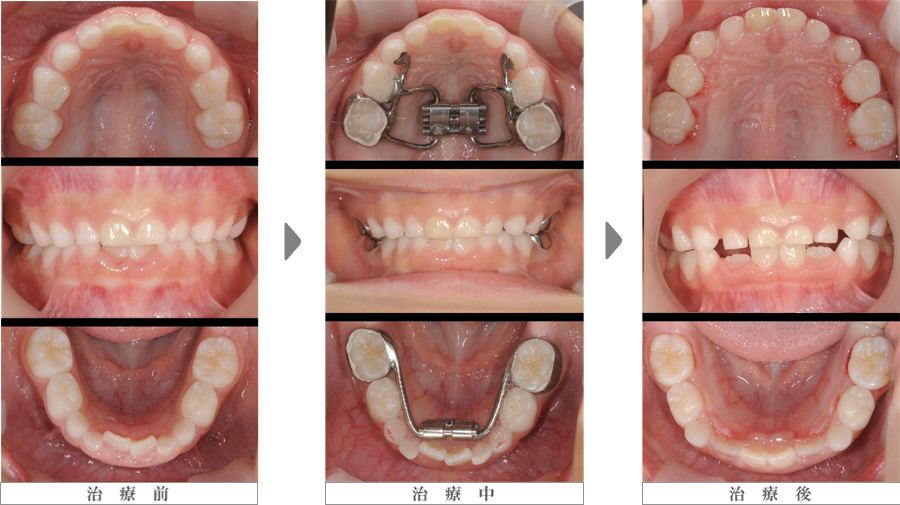

急速拡大装置

写真左列:治療開始前の上下前歯部のスペース不足

写真中列:急速拡大装置装着直後

写真右列:保定期間を入れ7ヶ月後の拡大終了時